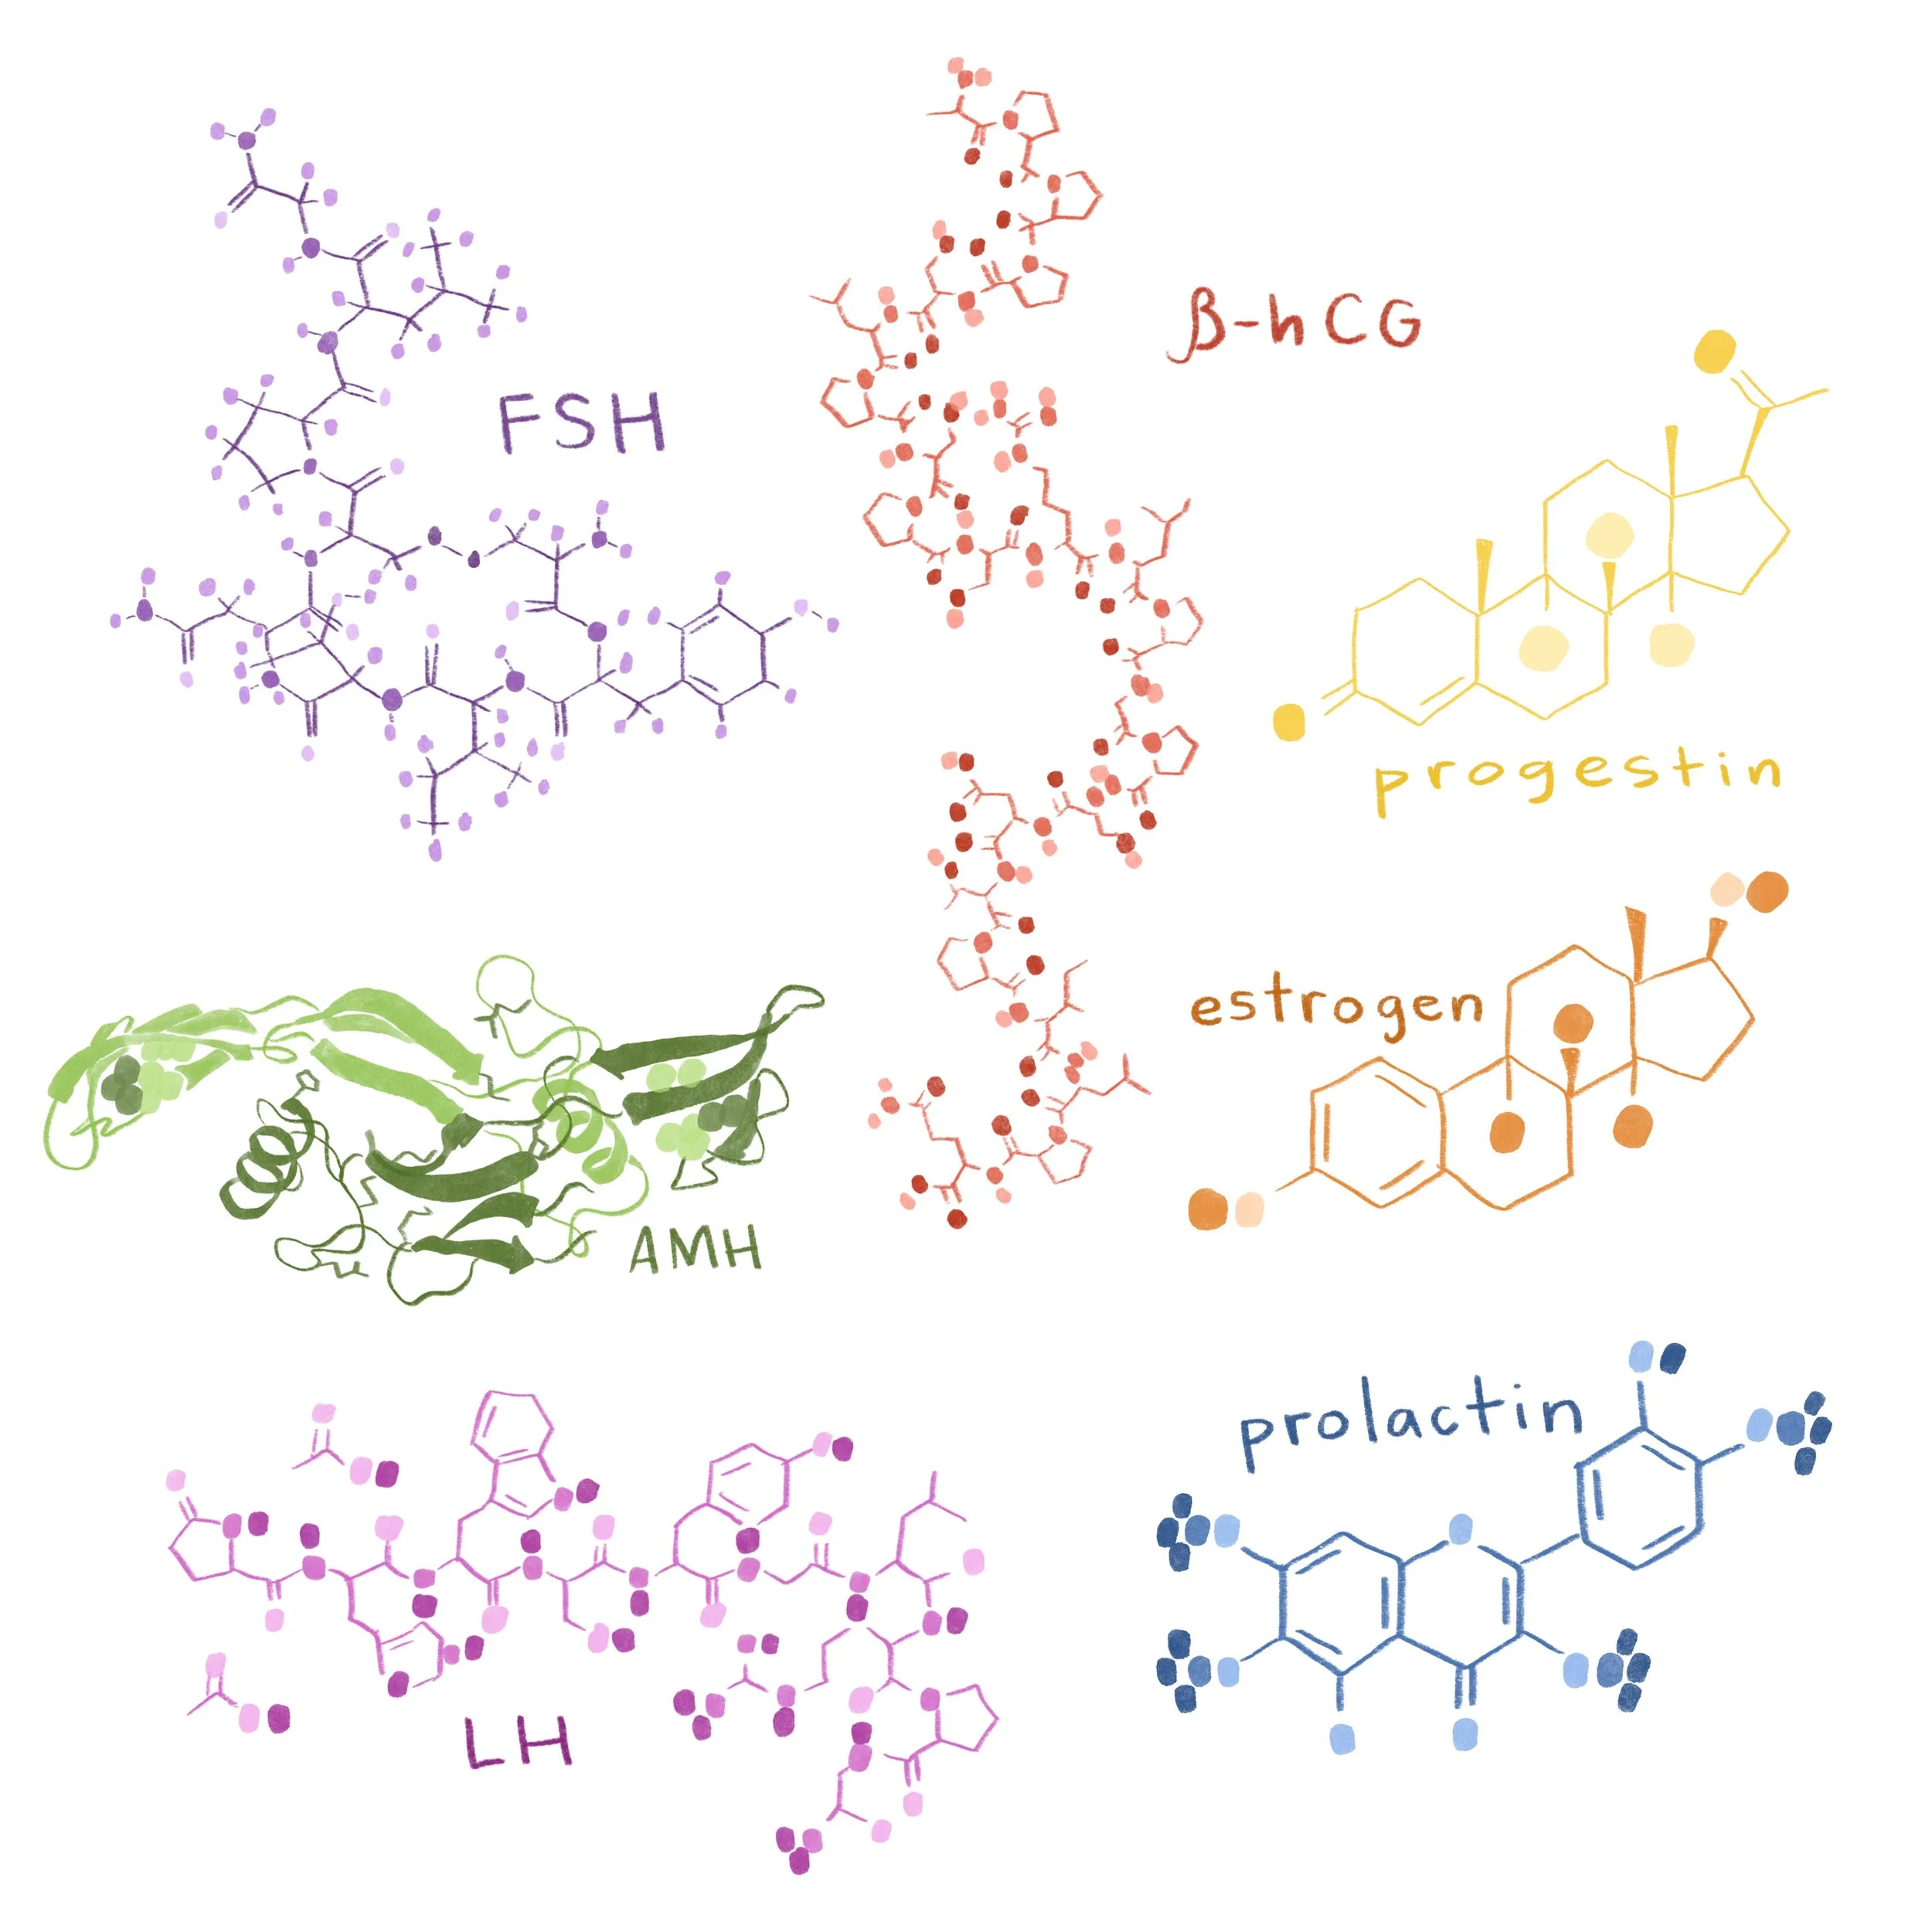

I created watercolor-style digital illustrations for an educational series on reproductive health called “How to Start a Family” for parents.com.

Digital watercolor artwork, 2022.

Fertility hormones

Fertility Hormones